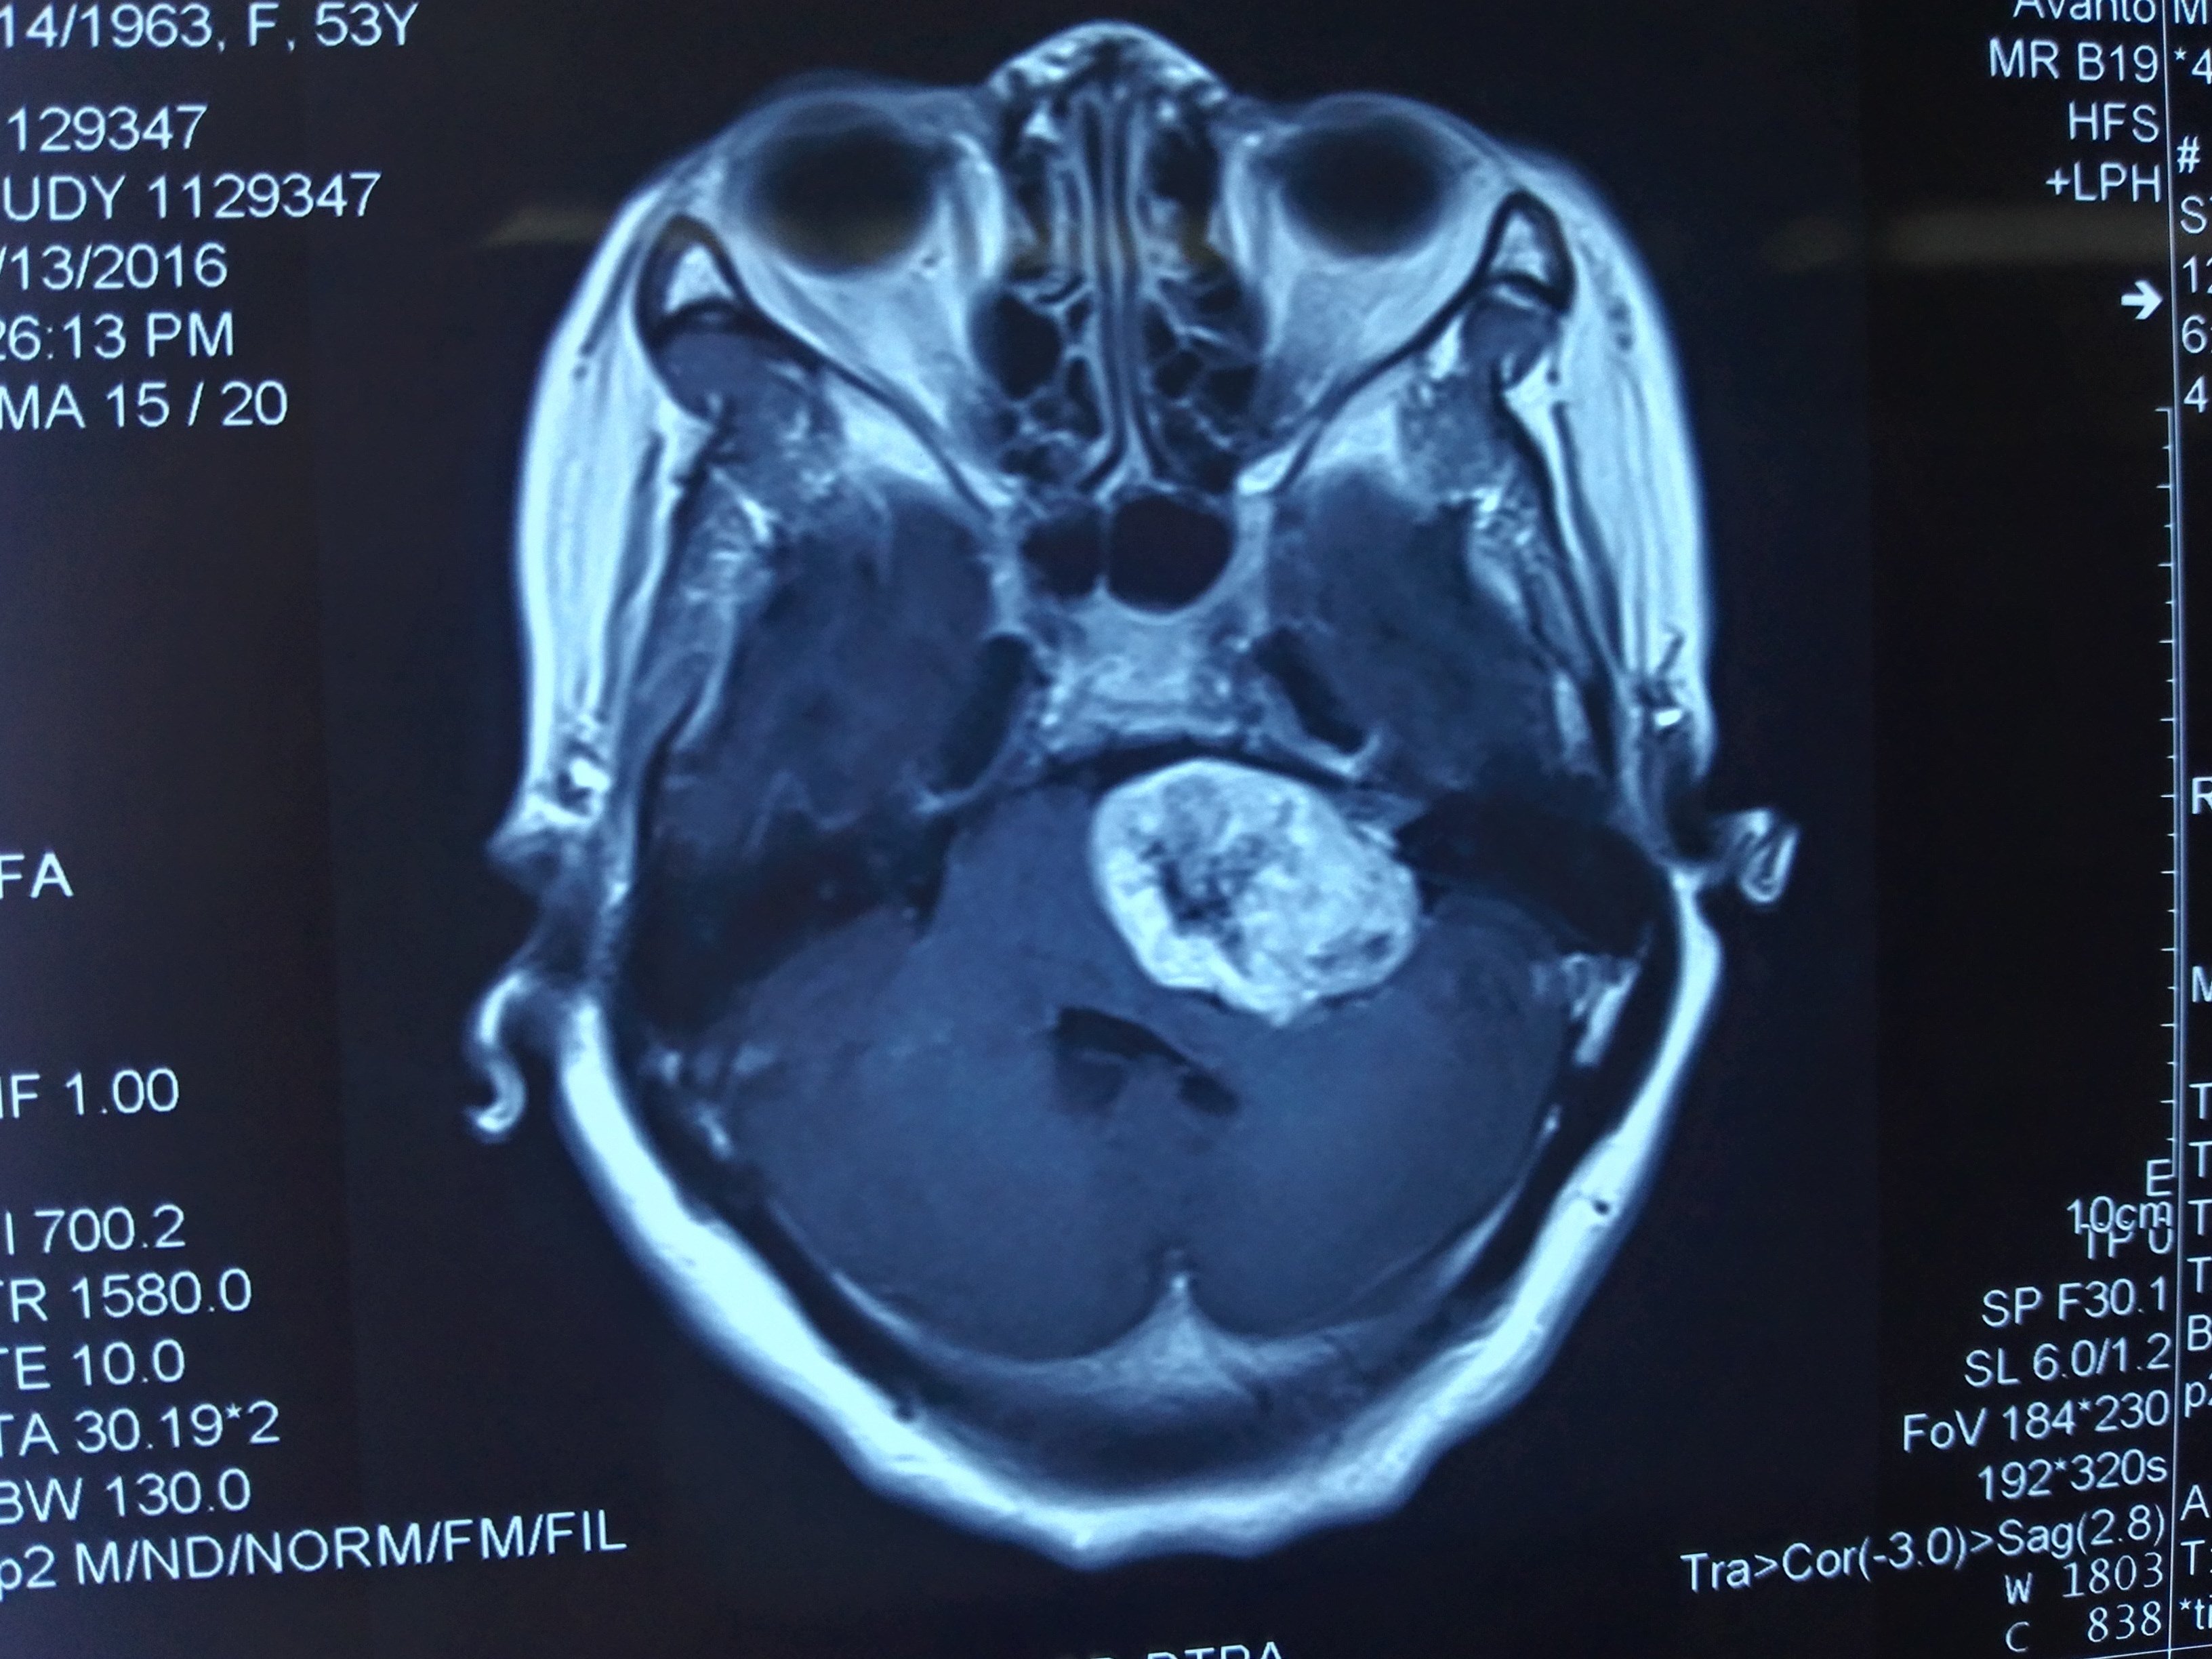

聽神經(jīng)瘤手術(shù)中的神經(jīng)保護是重點也是難點。因為長期受到腫瘤的壓迫,面神經(jīng)和蝸神經(jīng)常呈明顯的扇形變薄,甚至薄如蟬翼,給術(shù)中的解剖保留及功能保留造成很大困難。國內(nèi)外的研究顯示,面及蝸神經(jīng)的變形程度和腫瘤的大小密切相關(guān),腫瘤越大,腫瘤和神經(jīng)毗鄰的關(guān)系就越復(fù)雜,不確定因素就越多。另外,隨著腫瘤的持續(xù)進展,患者往往殘余聽力逐漸喪失,面神經(jīng)功能也呈減弱表現(xiàn)。因此,從神經(jīng)保護的角度出發(fā),國內(nèi)外的主流觀點建議盡早手術(shù),在較小的腫瘤體積下,在經(jīng)驗豐富的醫(yī)學(xué)中心,具有更高的神經(jīng)功能保留率,可維系更好的術(shù)后生活質(zhì)量。夏海堅主任醫(yī)師團隊龍年春節(jié)前成功治愈一典型病例。該患者中年女性,因右側(cè)耳鳴1年,聽力下降1月入院,經(jīng)磁共振證實,右側(cè)聽神經(jīng)瘤診斷明確,Koos分級2級,且患側(cè)尚存有用聽力。對于此類病人,盡早手術(shù)無疑是首選,手術(shù)是保留殘余聽力的唯一可能性。經(jīng)過詳細的方案制定,尚需要精細的方案落實。在切除腫瘤同時,準確判斷毗鄰面神經(jīng)及蝸神經(jīng)的位置,并給予精準的保留需要設(shè)備及經(jīng)驗的加持。在術(shù)中神經(jīng)電生理的輔助下,借助手術(shù)顯微鏡和動力系統(tǒng),夏海堅主任醫(yī)師準確磨開內(nèi)聽道后壁,確定腫瘤-神經(jīng)邊界后,利用超聲吸引分塊全切腫瘤,并妥善保留面神經(jīng)及蝸神經(jīng),術(shù)中電生理提示神經(jīng)功能良好。術(shù)后患者恢復(fù)和術(shù)中情況相符,順利度過圍手術(shù)期,無任何神經(jīng)功能缺損,面神經(jīng)功能良好(HBⅠ級),聽力同術(shù)前,可用患側(cè)接聽電話。純音測聽及言語識別率復(fù)查證實患側(cè)實用聽力完全保留,達AAO-HNSA級,從而維系了很高的生活質(zhì)量。因此,該例的診療過程進一步提示,聽神經(jīng)瘤確診后早期治療,獲益更多。重醫(yī)附一院神經(jīng)外科作為首批國家臨床重點專科和重慶市神經(jīng)外科質(zhì)控中心,具有悠久的歷史和優(yōu)秀的傳承。感謝各位病員朋友們的信任,我和我的團隊將繼續(xù)竭盡全力,為您的健康努力。